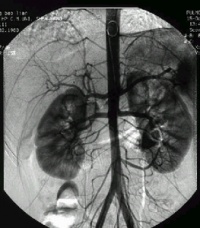

脑血管畸形影像

脑动脉造影

脑动静脉畸形有以下典型表现:①显示畸形血管。这是特征表现,呈一团管径相仿相互纠缠的迂曲扩张血管。畸形血管团的范围可小如指甲,大如手掌,多见大脑半球皮质.②异常粗大的供养动脉和引流静脉伴局部循环加快。此为局部血流短路的表现。③血流分流现象:造影剂随血流经畸形血管的短路大量流入静脉,因此,血管畸形部分因血流量增加而显影十分清楚。④血肿的表现:血管破裂出血致脑内血肿,血肿的主要表现为局部占位征象,一股脑部动静脉畸形无血肿时,脑血管不出现占位征象,脑血管不移位。